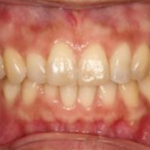

メタル修復の審美障害および二次カリエスに対しセラミックインレーへ置換した症例(50代女性)

治療前 治療後 相談内容 銀歯の見た目が気になること、詰め物の下の ...